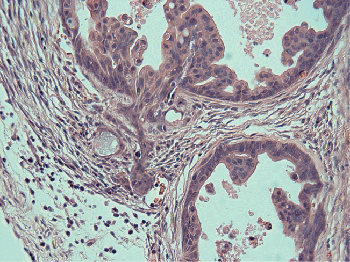

(above) Prostate cancer cells invading the surrounding stroma